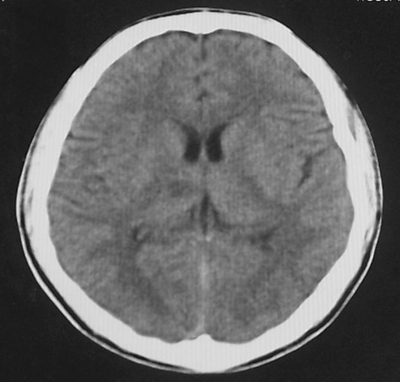

患者、男、18y,头痛5天入院。

左小脑、右丘脑区低密度影,无明显强化及占位表现,男18y,先考虑脑部炎性病变,如脑炎、血行播散性感染等,建议结合临床如脑脊液检验。

单独看左侧小脑半球的不规则形囊性低密度灶,从发病部位、年龄以及无强化、无占位效应的特点可以考虑毛细胞瘤型星形细胞瘤。同样,如果单独看右侧丘脑的近圆形低密度,也可以考虑囊变形星形细胞瘤。只是胶质细胞瘤一般为单发直接浸润、蔓延生长,而不是在脑内同时出现多个病灶,且瘤周没有一点儿水肿,暂时不予以考虑。

脑炎倒是首先可以考虑,只是临床症状、病史不很符合,建议狼兄仔细了解病史以及其他临床资料。

同时,现在已经进入冬天,一氧化碳中毒也需要考虑进去。不知道增强是什么时间做的,与平扫间隔几天?如果中间时间比较久而且进行吸氧等治疗,则平扫所示右侧颞叶密度比较低、右侧小脑半球以及脑桥也似有片囊状低密度,但在增强却没有发现就可以比较合理的解释了。